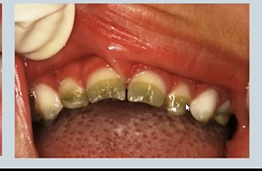

what is shown here?

enamel hypoplasia → not the same as hypo-mineralisation

Ameloblasts affected during development – less enamel formed Pits, grooves, thinning

enamel hypoplasia vs hypomineralisation

hypo-mineralisation is when you get the correct thickness of enamel but its softer and wears away faster

hypoplasia - structure is okay - but thinner, incomplete or pitted